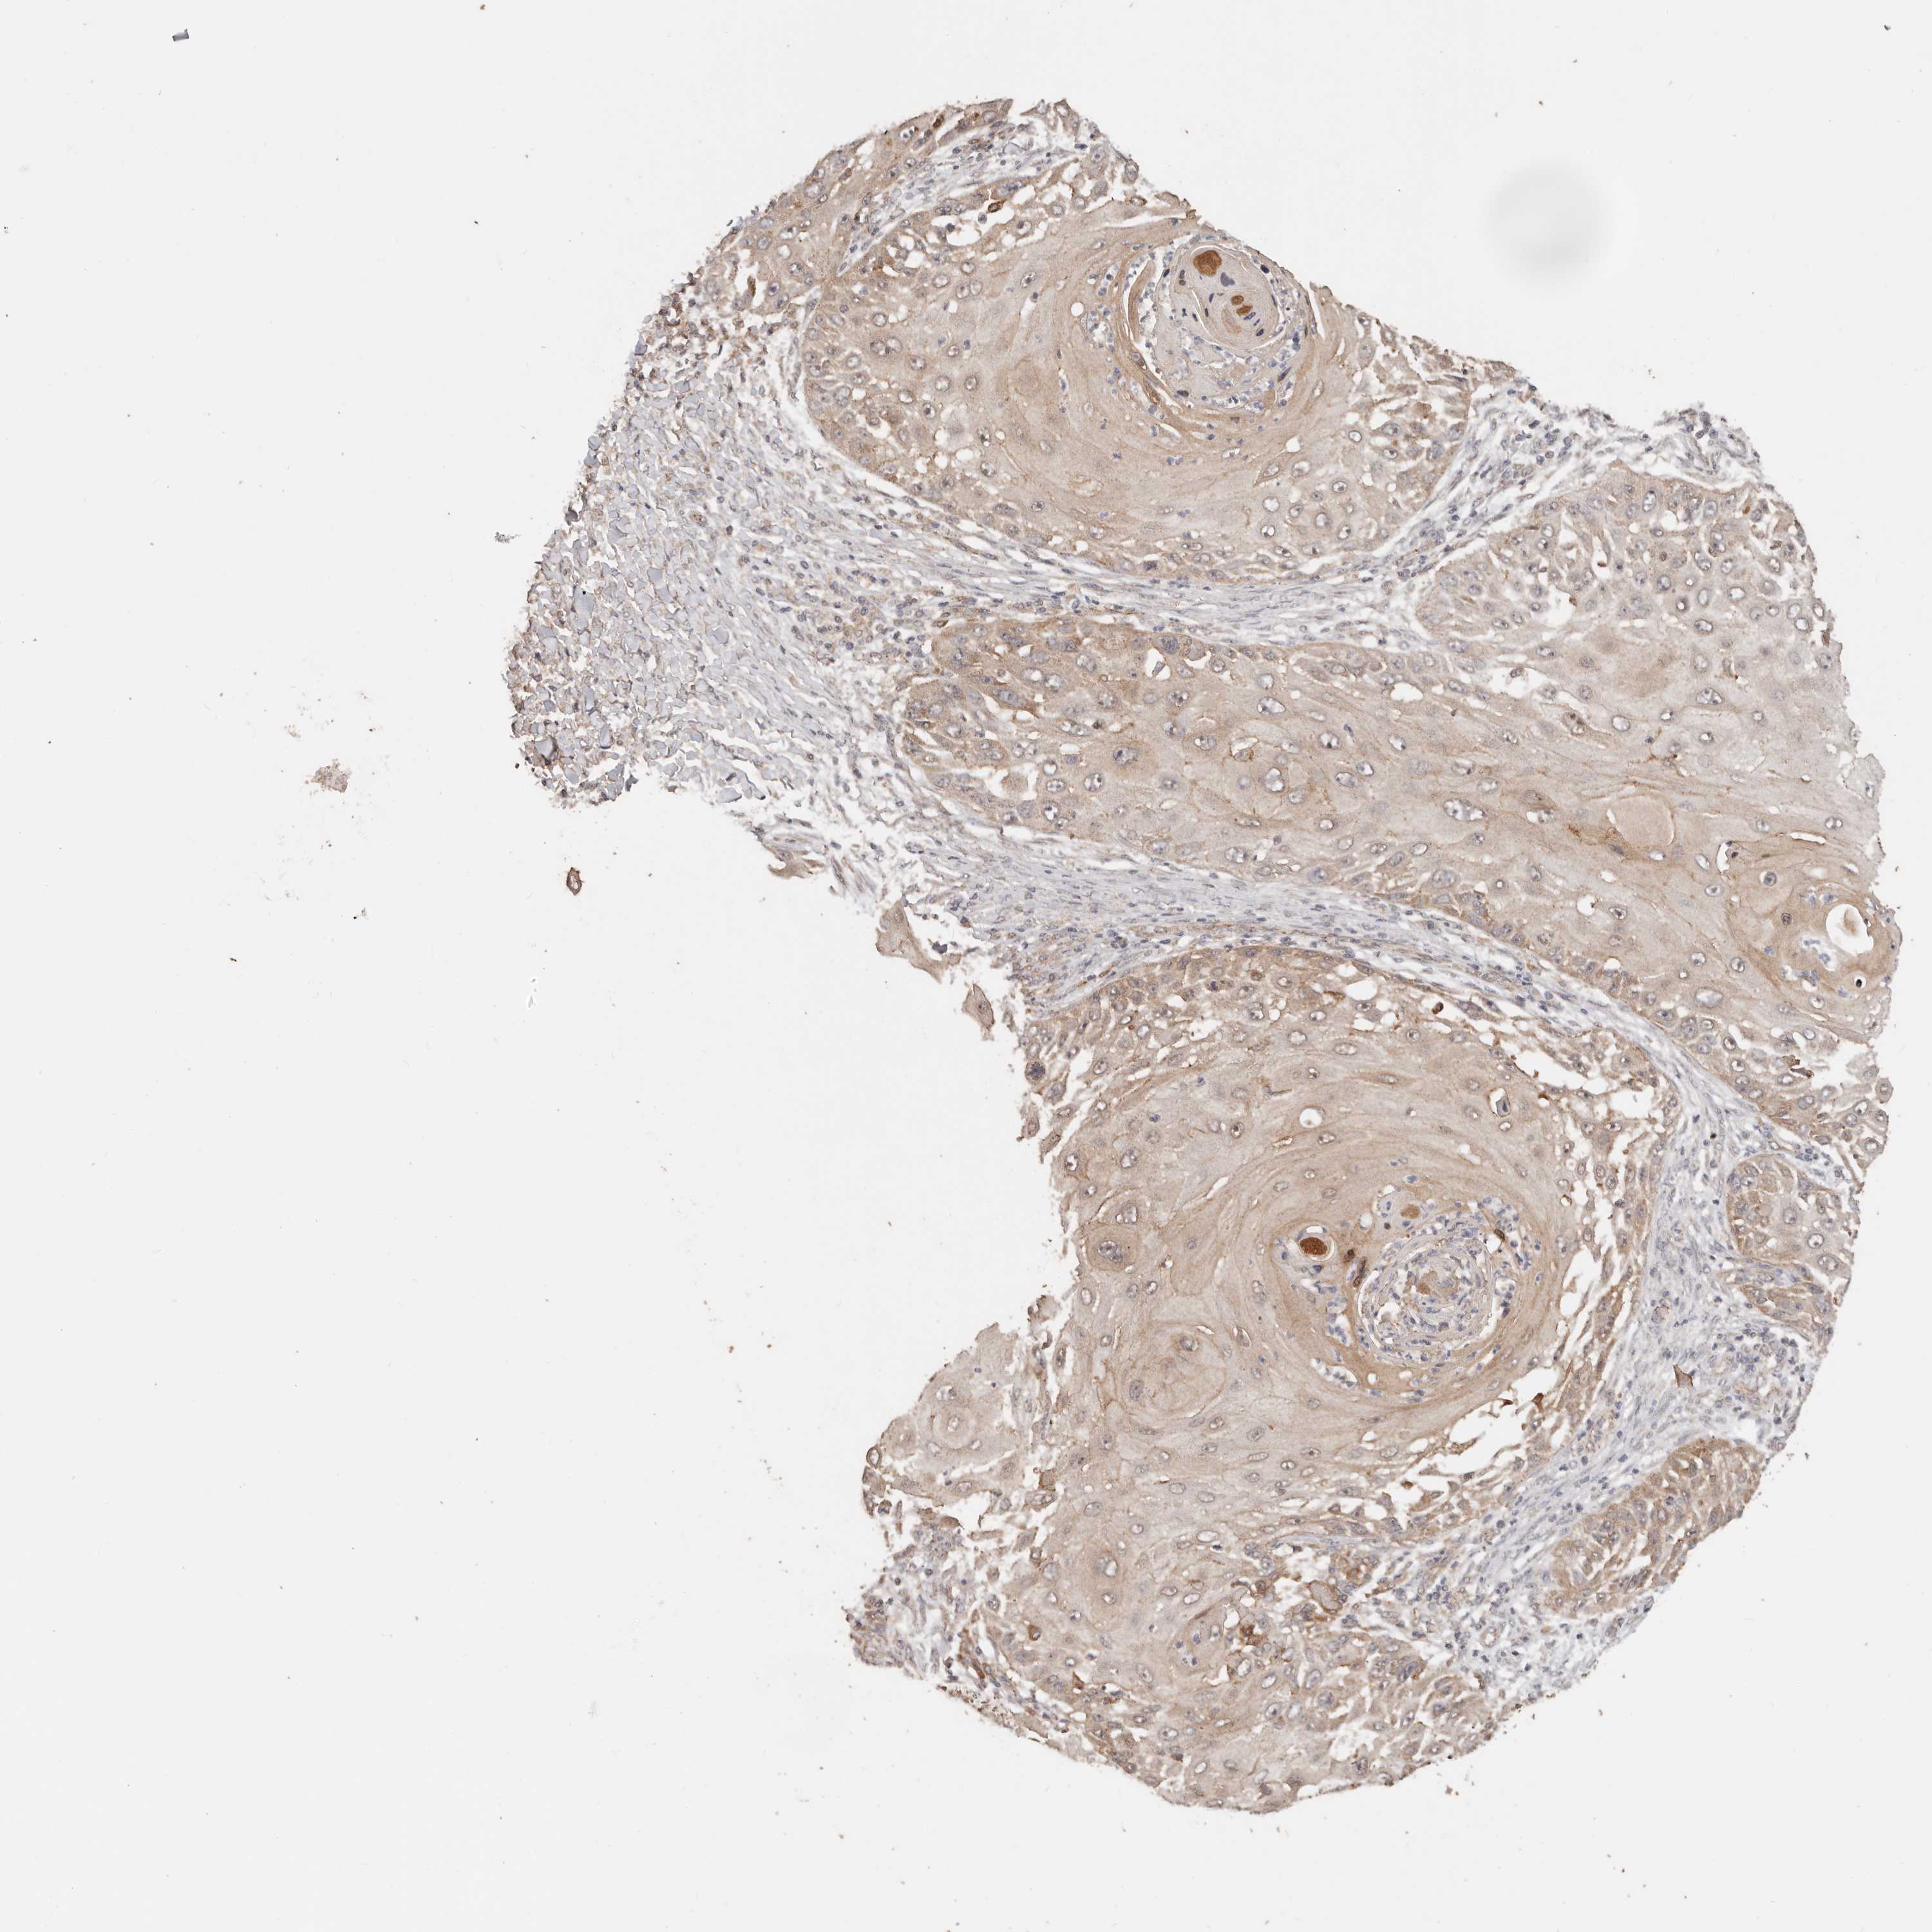

SKIN CANCER - Protein expressioni

A mouse-over function shows sample information and annotation data. Click on an image to view it in a full screen mode. Samples can be filtered based on level of antibody staining by selecting one or several of the following categories: high, medium, low and not detected. The assay and annotation is described here.

Antibody stainingi

Antibody staining in the annotated cell types in the current human tissue is reported as not detected, low, medium, or high, based on conventional immunohistochemistry profiling in selected tissues. This score is based on the combination of the staining intensity and fraction of stained cells.

Each image is clickable and will lead to virtual microscopy that enables deeper exploration of all samples and also displays staining intensity scores, fraction scores and subcellular localization as well as patient and tissue information for each sample.

Basal cell carcinoma

Squamous cell carcinoma, NOS

Squamous cell carcinoma, metastatic, NOS

Adnexal tumor, benign